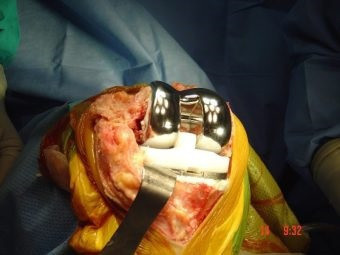

Revisión de prótesis de rodilla

Envíado por Dr. Ricardo Antonio Gómez G.